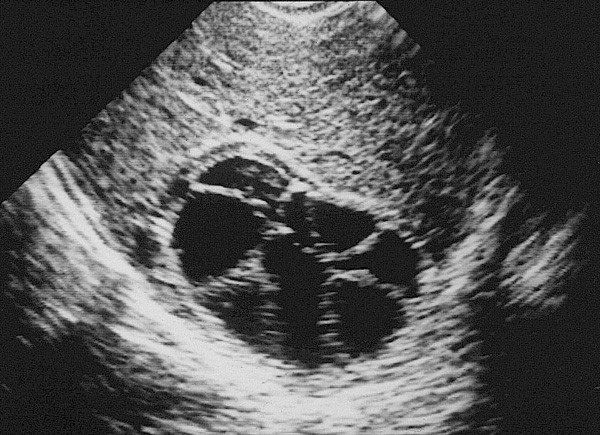

- Diaqnozu dəqiqləşdirmək üçün Qc venaları yoxlanılmalıdır. Bunun üçün dopler USM, KT-angioqrafiya, MRT-angioqrafiyalar və ya kontrastlı venoqrafiya edilir.

PVT diaqnozunu dəqiqləşdirmək üçün portoqrafiya aparılır – Doppler USM, KT və ya MRT angioqrafiya.

- Doppler USM;

Portoqrafiya – Doppler USM, KT və ya MRT angioqrafiya;